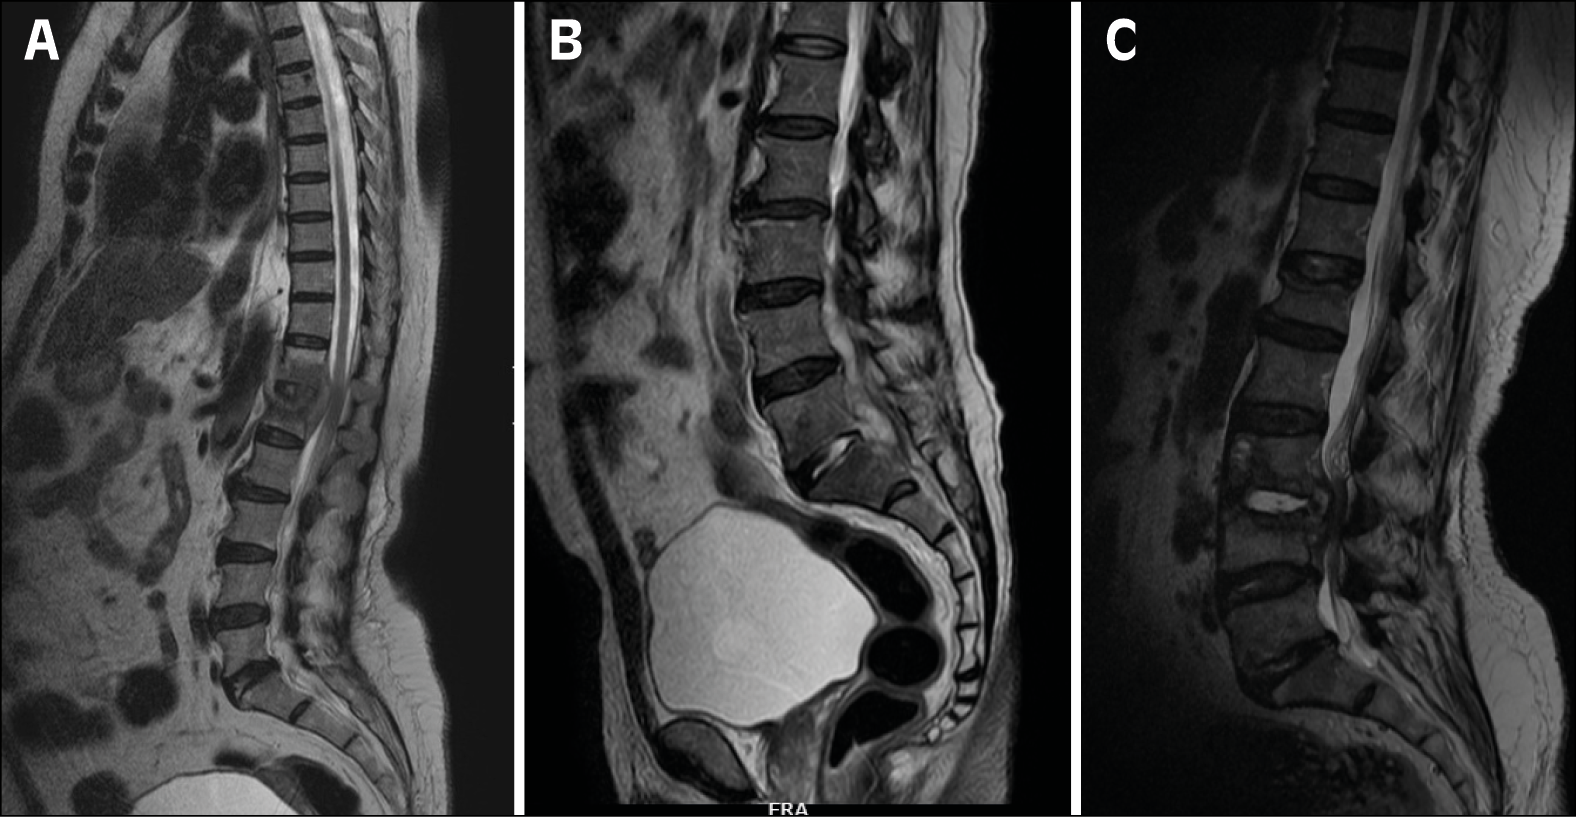

MRI scans

Magnetic Resonance Imaging (MRI) revealed significant abnormalities across various conditions. In the case of tubercular spondylodiscitis, changes were observed at the T12-L1 vertebrae (Figure 2A), with GenExpert® and histopathology confirming the presence of M. tuberculosis. The brucella antigen test returned positive for the patient with spondylodiscitis at L3-L4 (Figure 2B). In another patient with pyogenic spondylodiscitis (Figure 2C), a culture from the disc space tested positive for Staphylococcus aureus.

Figure 2 - Magnetic Resonance Imaging of different etilogies.

2A. Tubercular spondylodiscitis at T12-L1,

2B. L3-L4 spondylodiscitis.

2C Pyogenic spondylodiscitis.